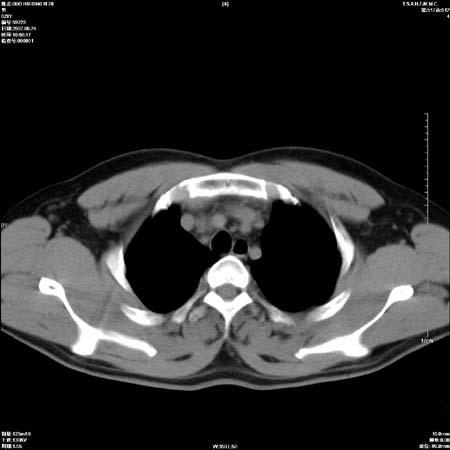

男性,28岁,体检发现左肺病变,患者只有背部隐痛感,哀哉,真不忍心下诊断啊。

左肺门区软组织肿块,左肺上叶支气管开口消失,纵隔内见肿大淋巴结,考虑左中心型肺部,可以做纤支镜取病理确认.

左肺肺门区肿块影,分叶明显,左肺上叶支气管开口受压,纵隔内见肿大淋巴结,考虑左中心型肺癌。